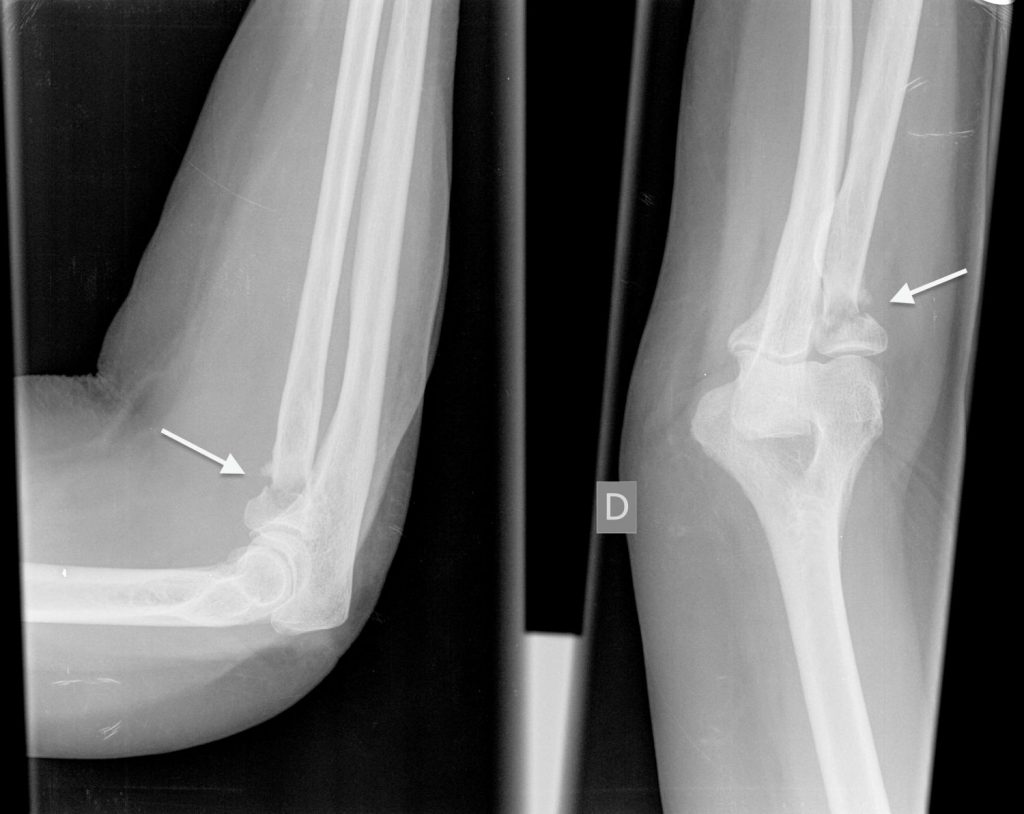

Fracturas de la cabeza y el cuello del radio (Figura 1)

El paciente suele notar mayor dolor cuando rota el antebrazo (cuando se gira la palma de la mano hacia arriba y hacia abajo). El tratamiento de esta fractura depende de la cantidad y el tamaño de los fragmentos del hueso. Las fracturas complejas a menudo necesitan cirugía para reparar y estabilizar los fragmentos, o para extraer o reemplazar la cabeza del radio si hay demasiados fragmentos de hueso.

Figura 1 - Fractura del cuello del radio.